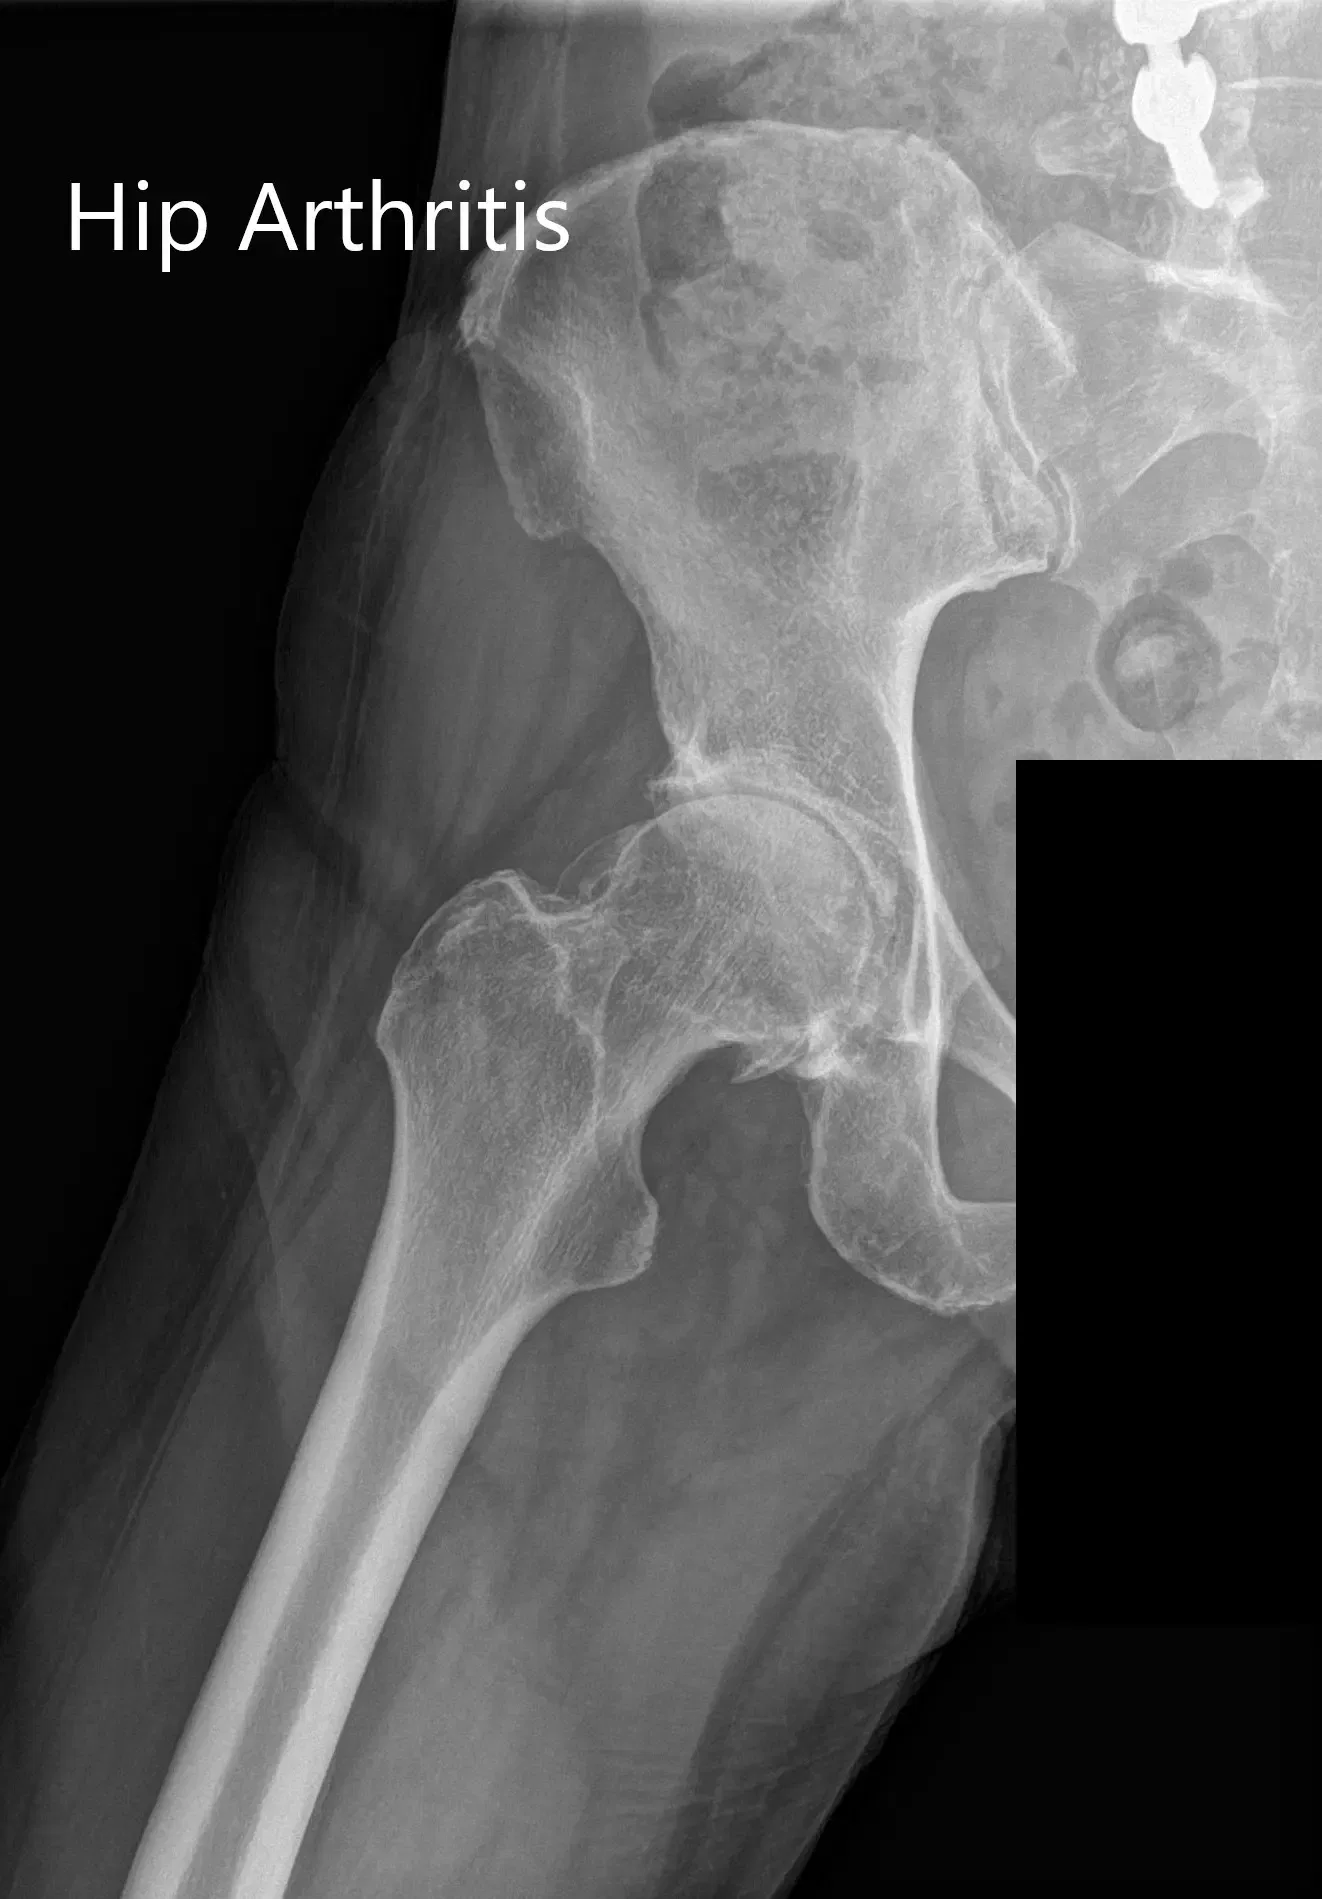

Las imágenes revelaron osteoartritis en la cadera derecha con reducción del espacio articular y osteófitos. Al paciente se le recomendó un reemplazo robótico total de cadera a la derecha. Los riesgos, beneficios y alternativas se discutieron extensamente con la paciente y ella estuvo de acuerdo con el plan.

Radiografía preoperatoria que muestra la vista de la parágrafe auricular y lateral de la cadera derecha.